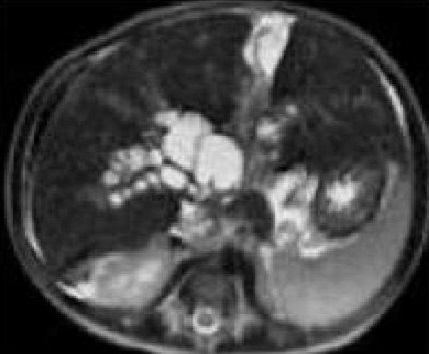

Image radiologique IRM

ponderation sur T2 d'une atresie de voie

bilisaire en coupe axiale : Aspect de lesion

kystique hyperintense au hile du foie , canal

hepatique droit et gauche sont dilates . Voie

biliaire intrahepatique et la vesicule sont en moin

de visible . |

Meme cas en coupe coronal (

frontal ) : Kyste du hile hepatique et atresie de

voie biliaire principale . Atresie de voie biliaire

de type 2 . Image IRM ponderation sur T2 |